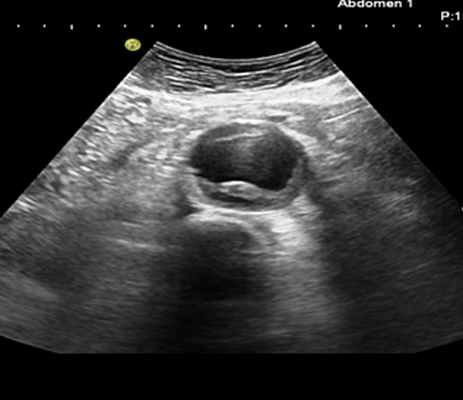

- Ультразвуковые методы исследования – при наличии аневризмы восходящего отдела аорты (I и II тип расслоения) или наличия пороков аортального клапана достаточно информативным методом диагностики является ЭХО-кардиография (УЗИ-сердца).

При расслоении III типа проводится УЗИ брюшной аорты.

Помимо гипертрофии миокарда левого желудочка, склеротически измененных створок аортального клапана и наличия его недостаточности I степени, обращало на себя внимание расширение восходящего отдела аорты до 4,5-5,1 см (на различных уровнях) (рис. 1). Исследование средних отделов восходящей аорты (рис. 2) позволяло выявить нитевидную, невыраженно флотирующую структуру, расположенную по передней стенке аорты, формирующую истинный и ложный каналы аорты, которые более детально верифицировались в режиме ЦДК (рис. 3). В слепом участке ложного канала определялись тромботические массы. При исследовании из супрастернального доступа в области дистального отдела восходящей аорты и ее дуги лоцировался участок отслоения интимы (рис. 4). В остальных отделах аорты, доступных для визуализации, патологии выявлено не было. Таким образом, ультразвуковое исследование сердца позволило диагностировать расслаивающую аневризму восходящего отдела и дуги аорты (тип II по De Bakey). Проведенная МСКТ подтвердила данный диагноз (рис. 5).

Расслоение начальных отделов аорты может быть определено при помощи трансторакальной или чреспищеводной ЭХО-КГ.